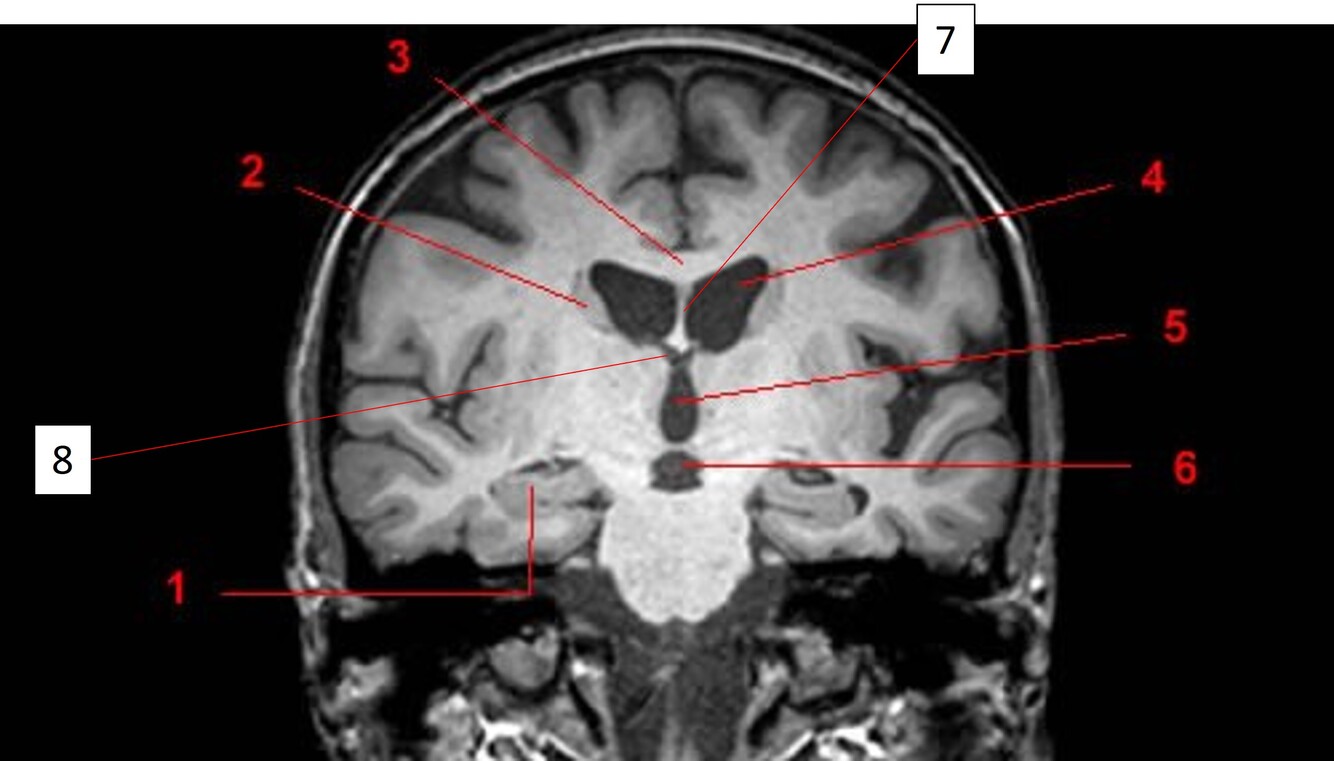

Label 2,3,4,5,7,8

A

2=Rt Caudate nucleus

3=Corpus callosum

4=Lt lateral ventricle

5=Third ventricle

7= Septum Pellucidum

8= Rt Interventricular foramen